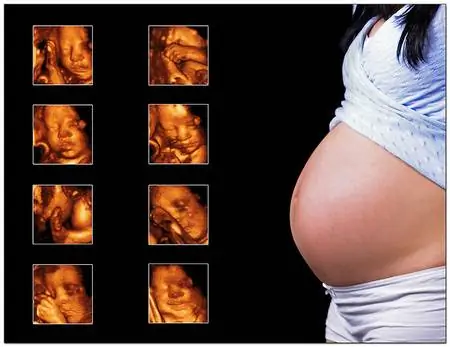

Сегодня у нас было УЗИ в 12 недель. У него тоже есть пальцы. Франко. Мы видели. Я не знаю, растрогался ли Роби, когда мы услышали его сердцебиение (это был приличный маленький ультразвуковой аппарат, и он тоже мог издавать звук), но у меня затуманились глаза, хотя я не эмоциональный человек. Они записали его на DVD за три тысячи. Я должен работать на износ, потому что я не могу даже в конце концов зарычать и назвать своего отпрыска бомжом или, что еще хуже, лепреконом… В любом случае, сначала мы пошли в патологию, потому что я плохо помнил пол..